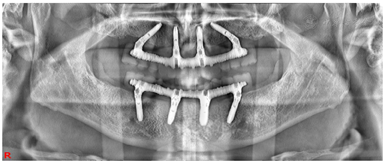

17、25、26、27、28、31、34、37、38、45、47、48缺失,缺牙区牙槽嵴低平。25、34、37拔牙创处于愈合期。口腔卫生情况欠佳,探诊深度PD 4-11mm,附着丧失1~10 mm,牙龈暗红,质地疏松,探诊出血,BOP%=100%,可探及连续龈下结石。18、16、11、21、32、33、35、36、41、42、43、44、46松动III度,15、14、13、12、22、23、24松动II度。前牙深覆牙合,右侧后牙咬合中性关系(图1)。颞下颌关节检查未见异常。影像学检查:初诊全景片显示余留牙牙槽骨水平性吸收至根尖1/3(图2)。术前CBCT截图显示15、14、13、12、22、23、24牙槽骨吸收至根中1/3水平,其余牙牙槽骨吸收至根尖1/3不等(图3)。

治疗过程(1)手术方案设计:拔除余留牙后,上颌拟在12、22植入2颗轴向植体,15、25植入2颗倾斜植体,下颌于32、42植入2颗轴向植体,35、45区域植入2颗倾斜植体,种植体倾斜角度小于45°,术后制作临时种植固定义齿,6月后戴终义齿(钛支架加丙烯酸树脂材料)。(2)种植一期术前测量垂直距离。术中拔除上下颌余留牙,分别于16-26、36-46区牙槽嵴顶近远中向切开牙龈黏膜,翻瓣,搔刮拔牙窝内炎性肉芽组织,平整牙槽嵴顶骨嵴,分别于12、15、22、25、32、35、42、45区定点,逐级备洞,12、22、32、42区轴向植入Nobel Speedy 4x13mm种植体,15、25、35、45区远中倾斜植入Nobel Speedy 4x15mm种植体。初期稳定性均达到35N·CM。15、25放置RP 5 mm 30°复合基台,12、22放置RP 3 mm 17°复合基台。32、42放置RP 2 mm 0°复合基台,35、45放置RP 4mm 30°复合基台,放置愈合帽,修整牙龈黏膜,缝合牙龈(图4)。术后拍摄全景片(图5)(3)即刻负重制取上下颌印模,制作蜡堤记录上下颌颌位关系,采用息止颌位法确定垂直距离,吞咽咬合法确定水平关系,转移颌位关系后,手术当日制作临时固定义齿修复至第二前磨牙并戴入固定,调整咬合接触(图6)。